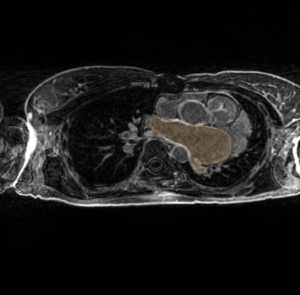

Hypertrophic LA Non-enhancing "no-reflow" LGE-MRI

Carma hypertrophy.png

Carma no reflow.png

Here the LA (blood pool delineated by the orange label mask) is quite a bit larger than normal; the left side (right side of the image) appears very dilated. In this image the LA wall (region surrounding the blood pool -- orange label mask) has dark regions of non-enhancement. Large bright regions surround the LA wall tissue (possibly edema from the ablation procedure).